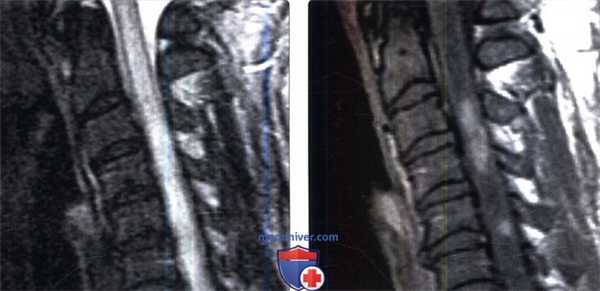

(Слева) Сагиттальный срез, Т1-ВИ шейно-грудного отдела позвоночника: признаки однородного усиления сигнала костного мозга грудных позвонков с достаточно хорошо выраженной переходной зоной этих изменений на уровне Т1-Т2, т. е. на уровне верхней границы области облучения.

(Справа) Сагиттальное Т1-ВИ с признаками гомогенной постлучевой жировой перестройки костного мозга грудных позвонков и четкими границами этих изменений, соответствующими границам области облучения.